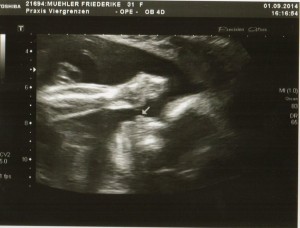

Heute war es mal wieder Zeit für die nächste Vorsorgeuntersuchung unseres Würmchens 1.0. Diesmal gab es das volle Programm, vor allem für die werdende Mutti. Neben des leckeren Zuckertests und der anschließenden Blutabnahme gab es noch eine Grippeschutzimpfung gratis obendrauf. Die Tests waren alle im Normalbereich.

US_Bild_11

Natürlich wurde unser Sohnemann auch wieder ausgiebig begutachtet und vermessen. Leider hat er sich heute nicht von seiner Schokoladenseite gezeigt und lag so ungünstig, dass diesmal nur ein recht unscharfes Profilfoto herauskam. Wir liegen aktuell bei stolzen 890g. Laut den aktuellen Vermessungen ist das Köpfchen etwas zu groß (2 Wochen voraus). Nun müssen wir abwarten wie sich das so entwickelt. Wird halt ein großer Denker mit ganz viel Grips werden 😉